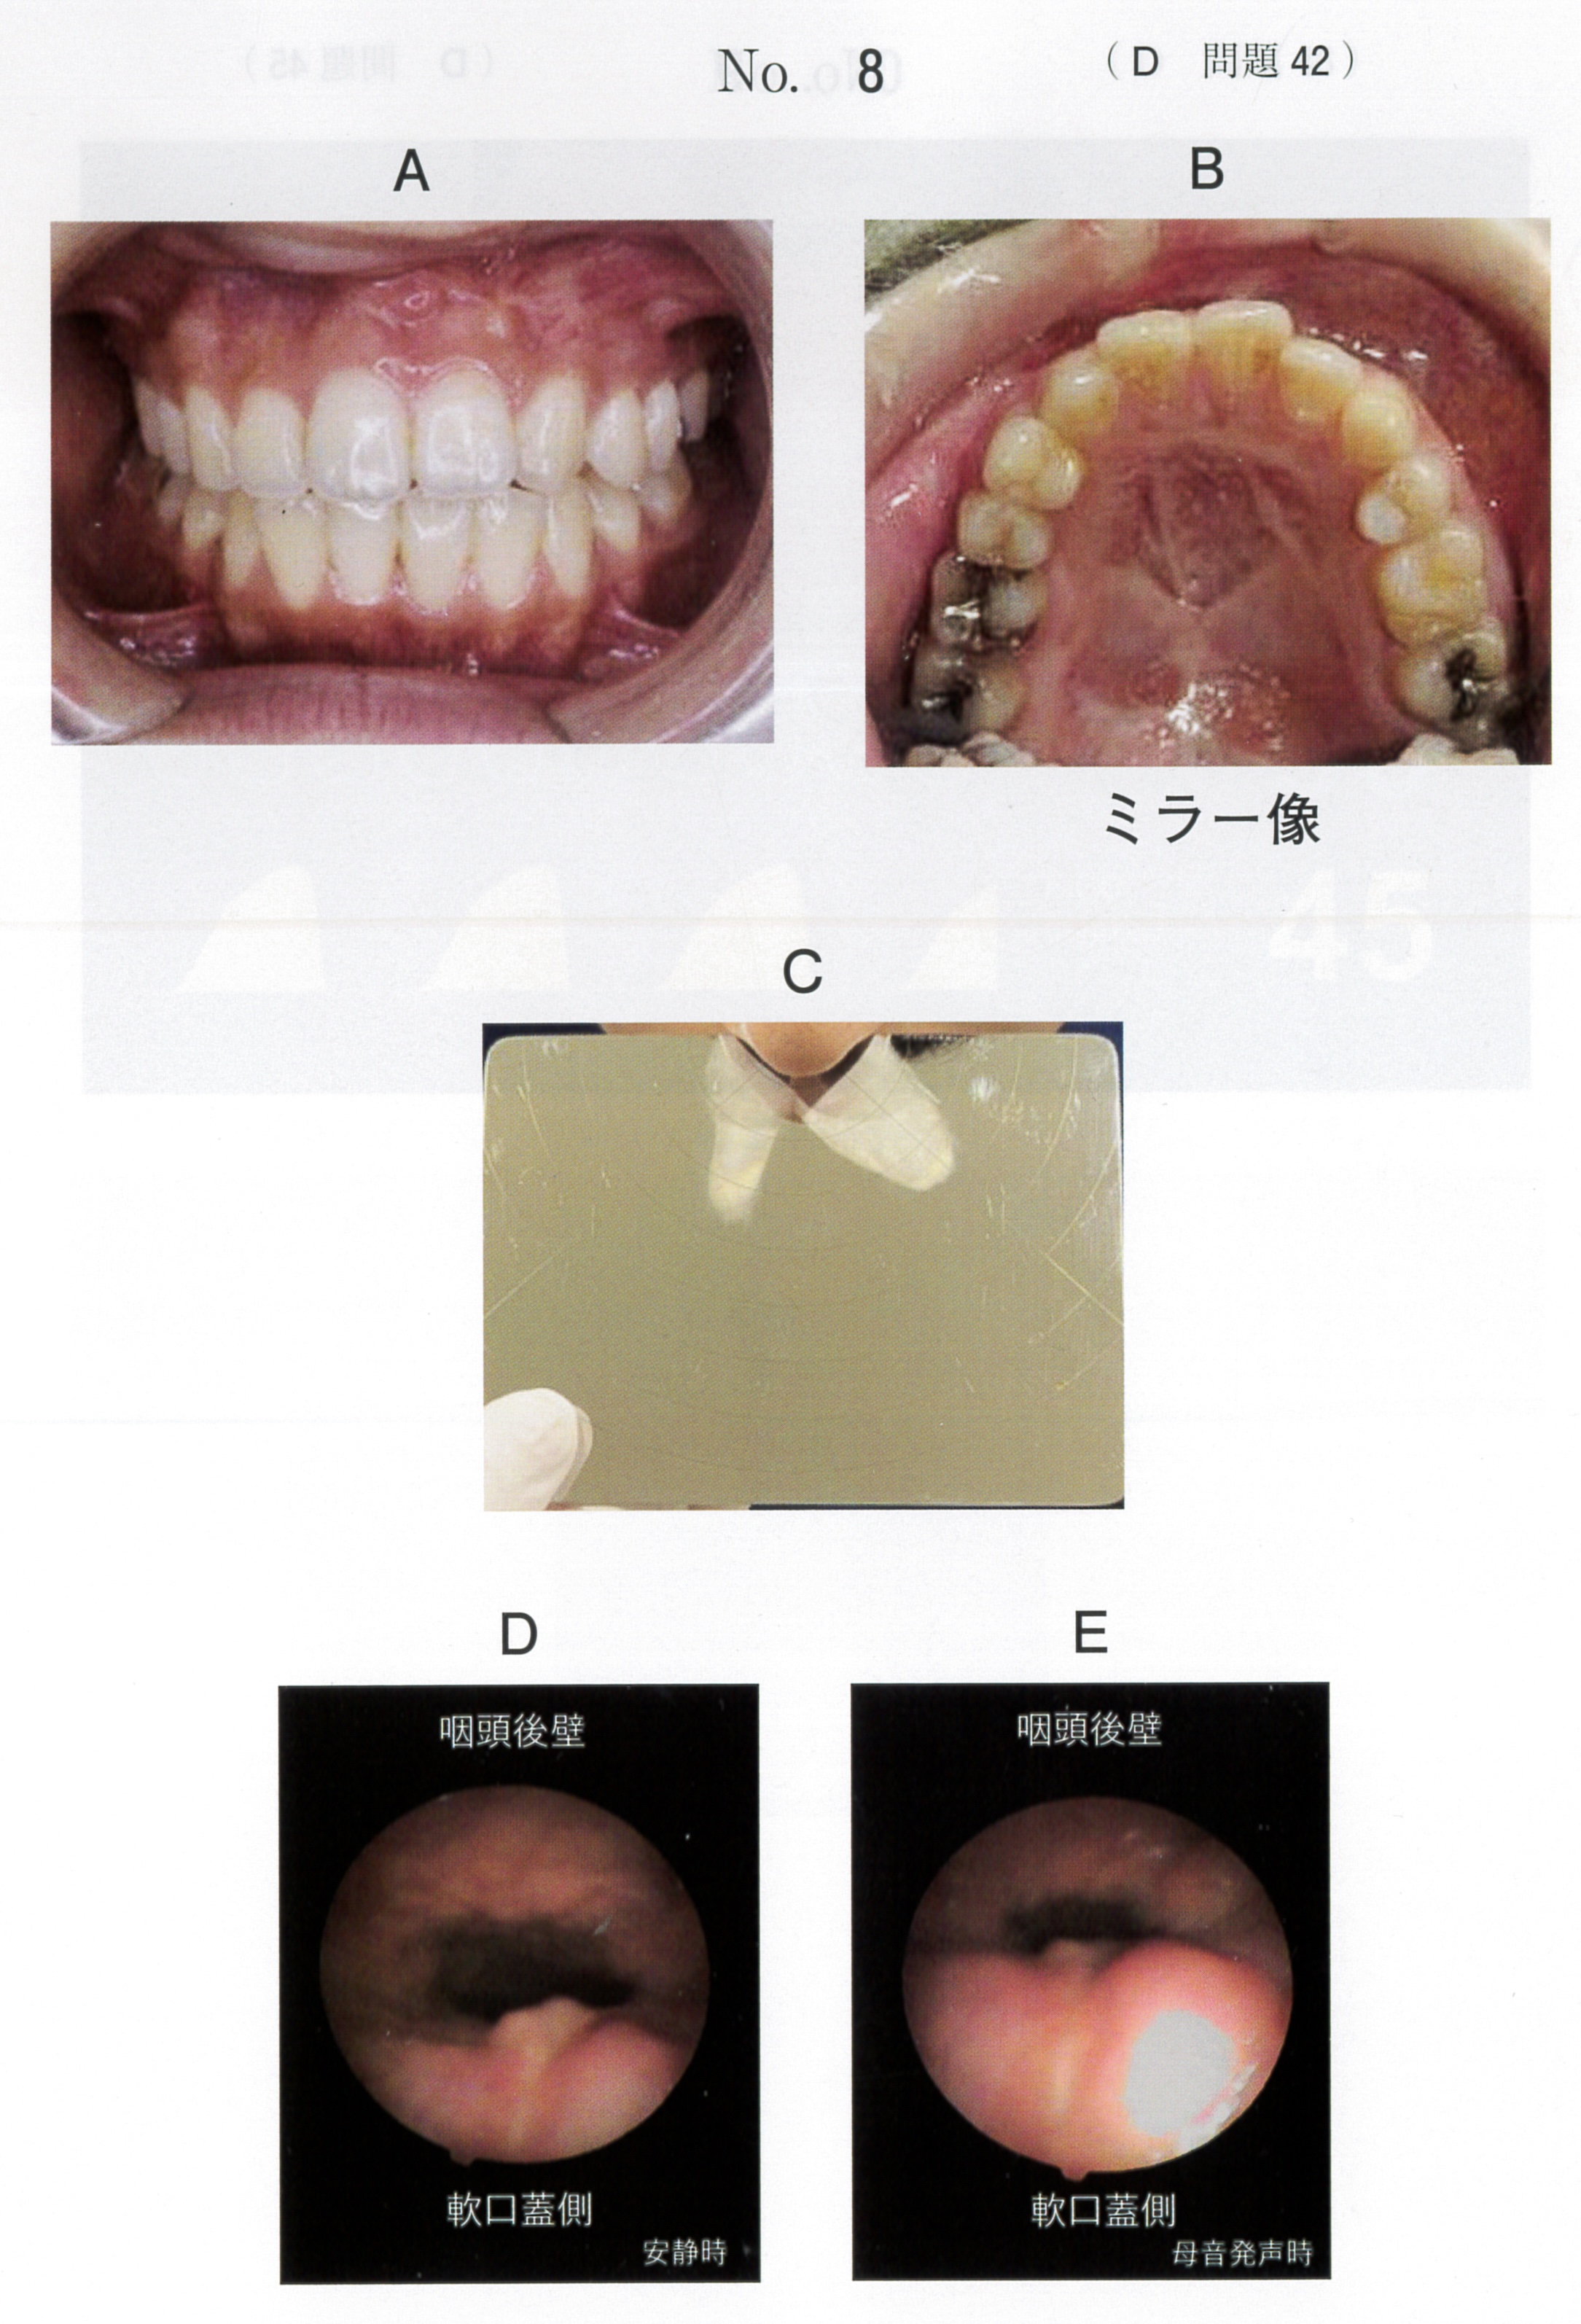

臨床医学に特化した国試対策テキスト。DES本校生限定資料 ① 小児歯科学(総括)P25② 臨床実技関連テキストP31③ 国試に出る症候群まとめP25状態)一切書き込み無し。裁断済み(神経質な方は控えてください)その他)ペット喫煙無し差し替え防止のため、返品返金不可。バラ売りの場合は、1冊子5000円とします。セット価格にしておきます。- タイトル: 国試に出る名詞整理まとめ- 内容: 臨床医学に関するテキストと資料- 形式: 印刷物- ページ数: 複数ページ- 対象: 医療従事者向け- 言語: 日本語ご覧いただきありがとうございます。